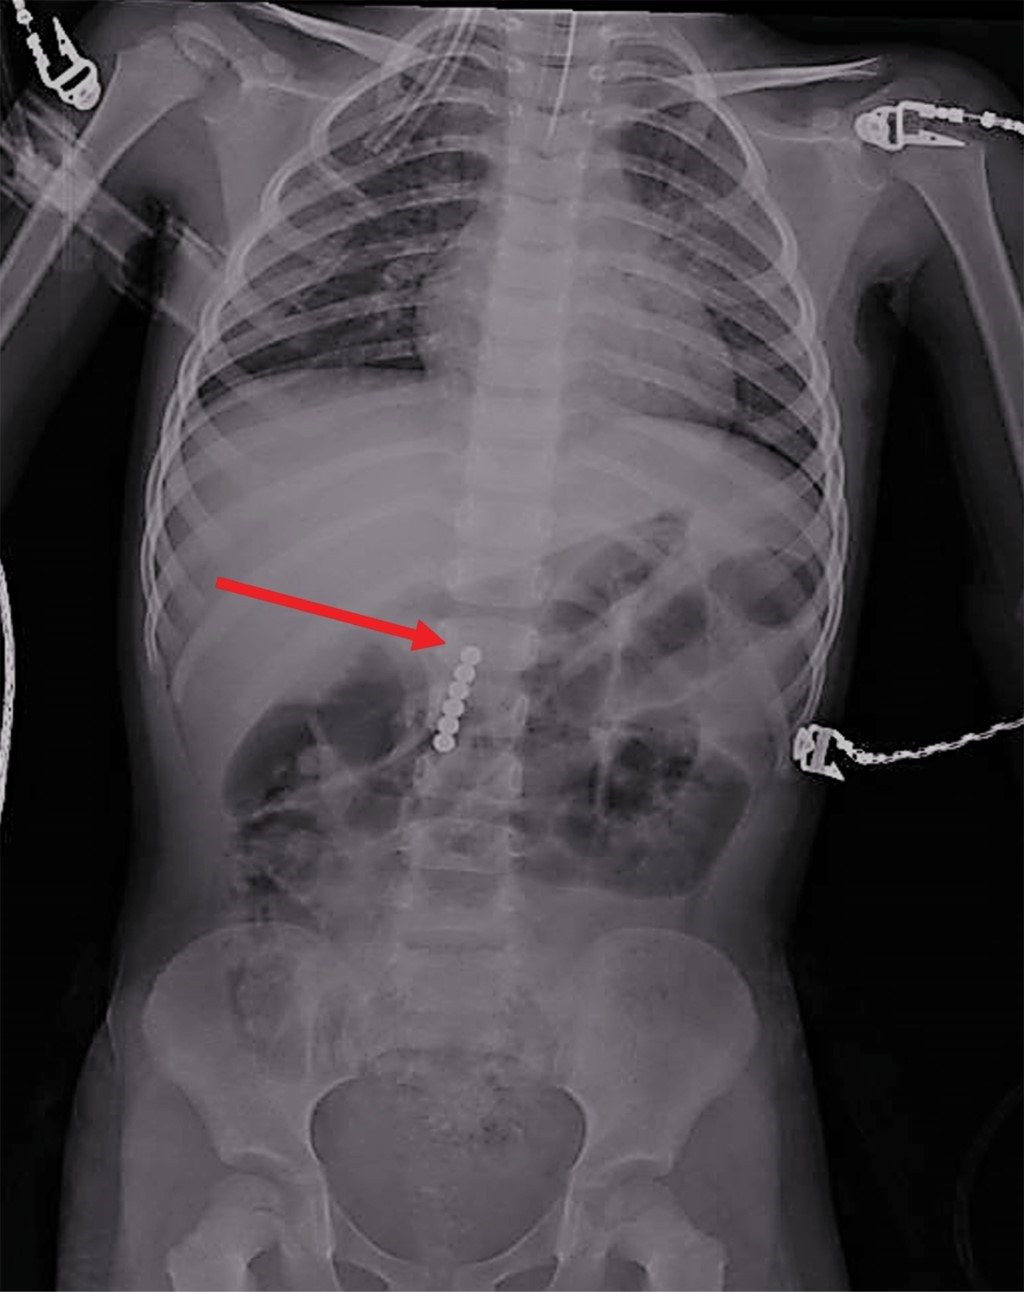

Se toma nueva radiografía de abdomen observando seis imanes más (Figura 5). Por sospecha de perforación, se realiza laparotomía exploradora encontrando que el epiplón cubre al estómago y al retirarlo se observa asa de intestino delgado pegada a la curvatura mayor del estómago. Al despegar el asa se aprecia un orificio en el intestino (localizado a 30 cm de la válvula ileocecal), el cual comunica con otro en el estómago. En esta porción intestinal se observan los seis imanes restantes (Figura 6). Se realiza resección de 6 cm de íleon con anastomosis término-terminal y en estómago se reavivan los bordes cerrando en dos planos. Se maneja con ayuno por cinco días, sonda nasogástrica, triple esquema antibiótico, omeprazol y analgésicos. La evolución es satisfactoria y se egresa a los siete días. Se le da seguimiento por seis meses permaneciendo asintomática.

Figura 5